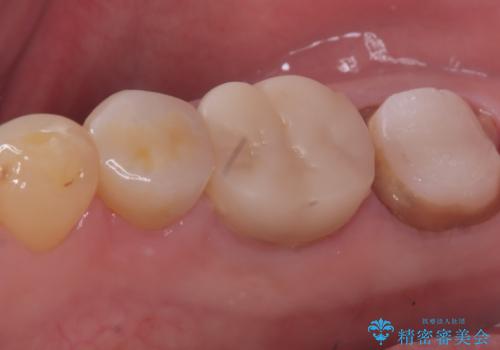

【セラミッククラウン】銀歯を白くしたい

- 主訴:笑った時に下の銀歯が目立つので、白いものに替えたい

失活歯に保険適応のメタルクラウンがセットされていました。

根尖病巣と根管内に破折ファイルを認め、ファイル除去は困難だということをお伝えし、根管治療・土台・クラウンのやり替えとなりました。

根管内破折ファイルの除去が難しいことから、近心根根尖部の洗浄が十分には行えない(病巣が消えない可能性がある)ことを了承いただき治療となりました。